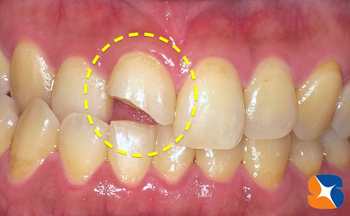

年末の急患30代の女性。主訴は、「転倒して前歯が欠けた。しみる。強度があり、長持ちする歯を年内に出来ますか?」でした。

神経の残したまま、セラミックの被せ物を装着する準備を開始。多彩な色見本と一緒に、お口の中の撮影は必須。毎晩、この写真を参考に前歯を製作しています。 続きを読む